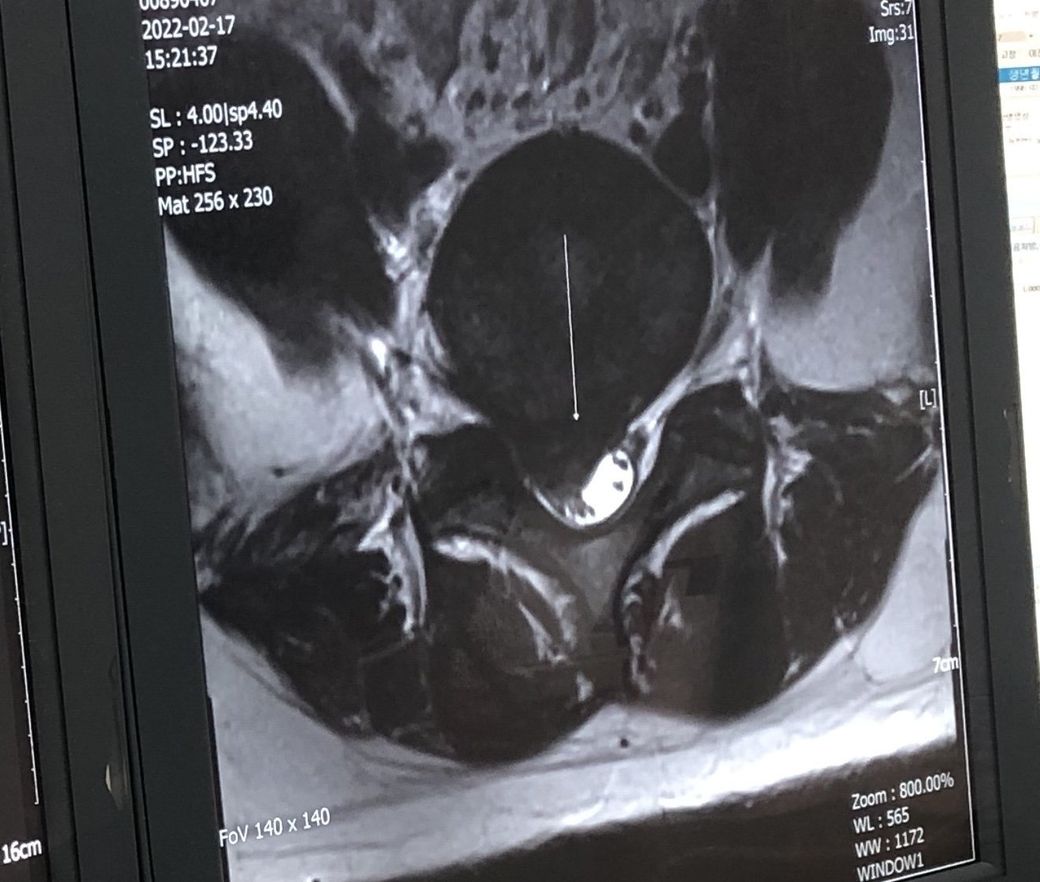

허리디스크 수술 해야할까요?보존치료도가능할까요?

27살 여자구요 주로 앉아서 일하고 고개와 허리를 굽혀 일합니다. 약 한달전부터 허리가아팟고 동네 정형외과애서 엑스레이를찍고 mri권유를 해서 더큰 정형외과로 갔습니다 .그병원에서도 엑스레이를 먼저찍었는데 아직 젊어서 괜찮을거라 하시며 영상판독은 나중에 하자며 약복용과 물리치료(골반견인) 해왔습니다. 그때부터 다리저림(절뚝거림) 과 엉치뼈쪽 고통과 앉을때와 서있을때도 고통이있어 결국 다니던 정형외과와 제휴?를 맺은 곳에서 영상을찍었는데 그 곳 의사분은 시술이나 수술을 고려해봐야할 정도라고 하셨고 영상씨디를 다시가지고와 정형외과에서 꼬리뼈주사(신경차단) 을맞고 수술이나 시술은 보류해보자면서 몇일이지났는데도 통증은 여전해 다시 병원을 갔는데 지금도 약이 쎈거라 하시면서 진통제를 더 처방해주셨는데 고통은 살짝 줄었지만 욱씬하고 얼얼한느낌은 계속납니다. 제가 꼭 수술이나 시술을 해야하는지 궁금하고 제증상이 심한건지 알고싶습니다.

허리 MRI자체만을 보자면 현재 디스크의 탈출 정도는 심한편입니다.

하지만 허리디스크의 수술을 결정함에 있어서 가장중요한 것은 환자분의 증상입니다.

현재 근력의 저하가 없는 상태라면 증상이 약물 및 신경차단술 등으로 호전이 있고참을만 하다면 경과관찰이 가능하지만 이러한 치료에도

효과가 없고 참을수 없는 통증이라면 이는 수술적치료를 통해 디스크를 제거해 주시는 것이 좋을것 같습니다.

• MRI 소견을 통해 보았을 때에 질문자님의 디스크 상태는 매우 심한 편으로 보입니다. 하지만 그와는 별개로 하지의 근력 저하나 감각 저하와 같은 신경학적 소견 없이 통증만 있는 상태라면 시술 보다는 코어 근육 강화, 체중 감소 등을 통해서 척추에 가해지는 부담 자체를 줄여 디스크의 호전을 기대해보시는 것이 근본적인 해결법입니다. 시술을 받으면 당장은 어느 정도 호전될 수 있지만 다시 디스크가 악화될 우려가 높습니다.